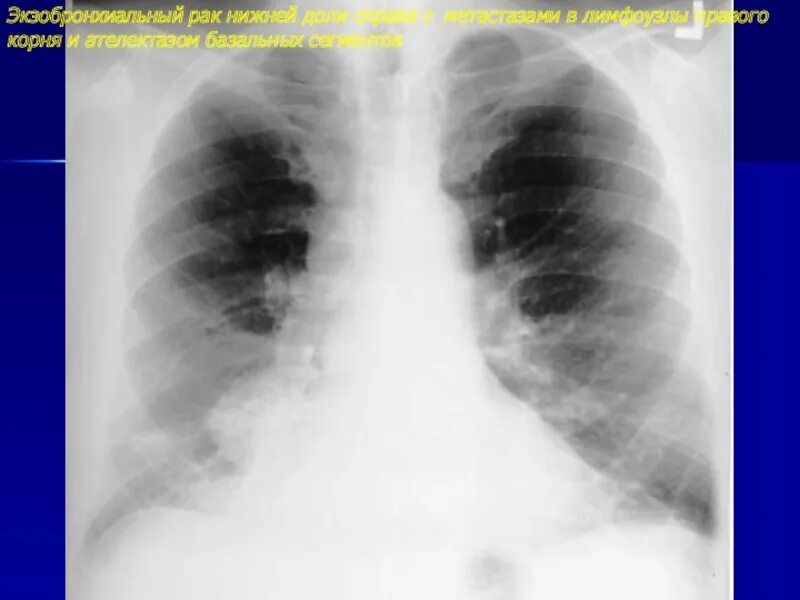

Метастазы в лимфоузлах легких